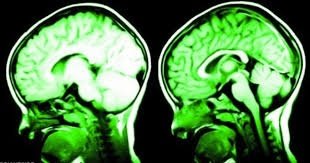

7 cách khiến não bộ hạnh phúc hơn

Tất nhiên, mỉm cười, ngủ trưa, chăm sóc con mèo, hít thở không khí trong lành, tiếp xúc nhiều hơn với ánh sáng mặt trời...